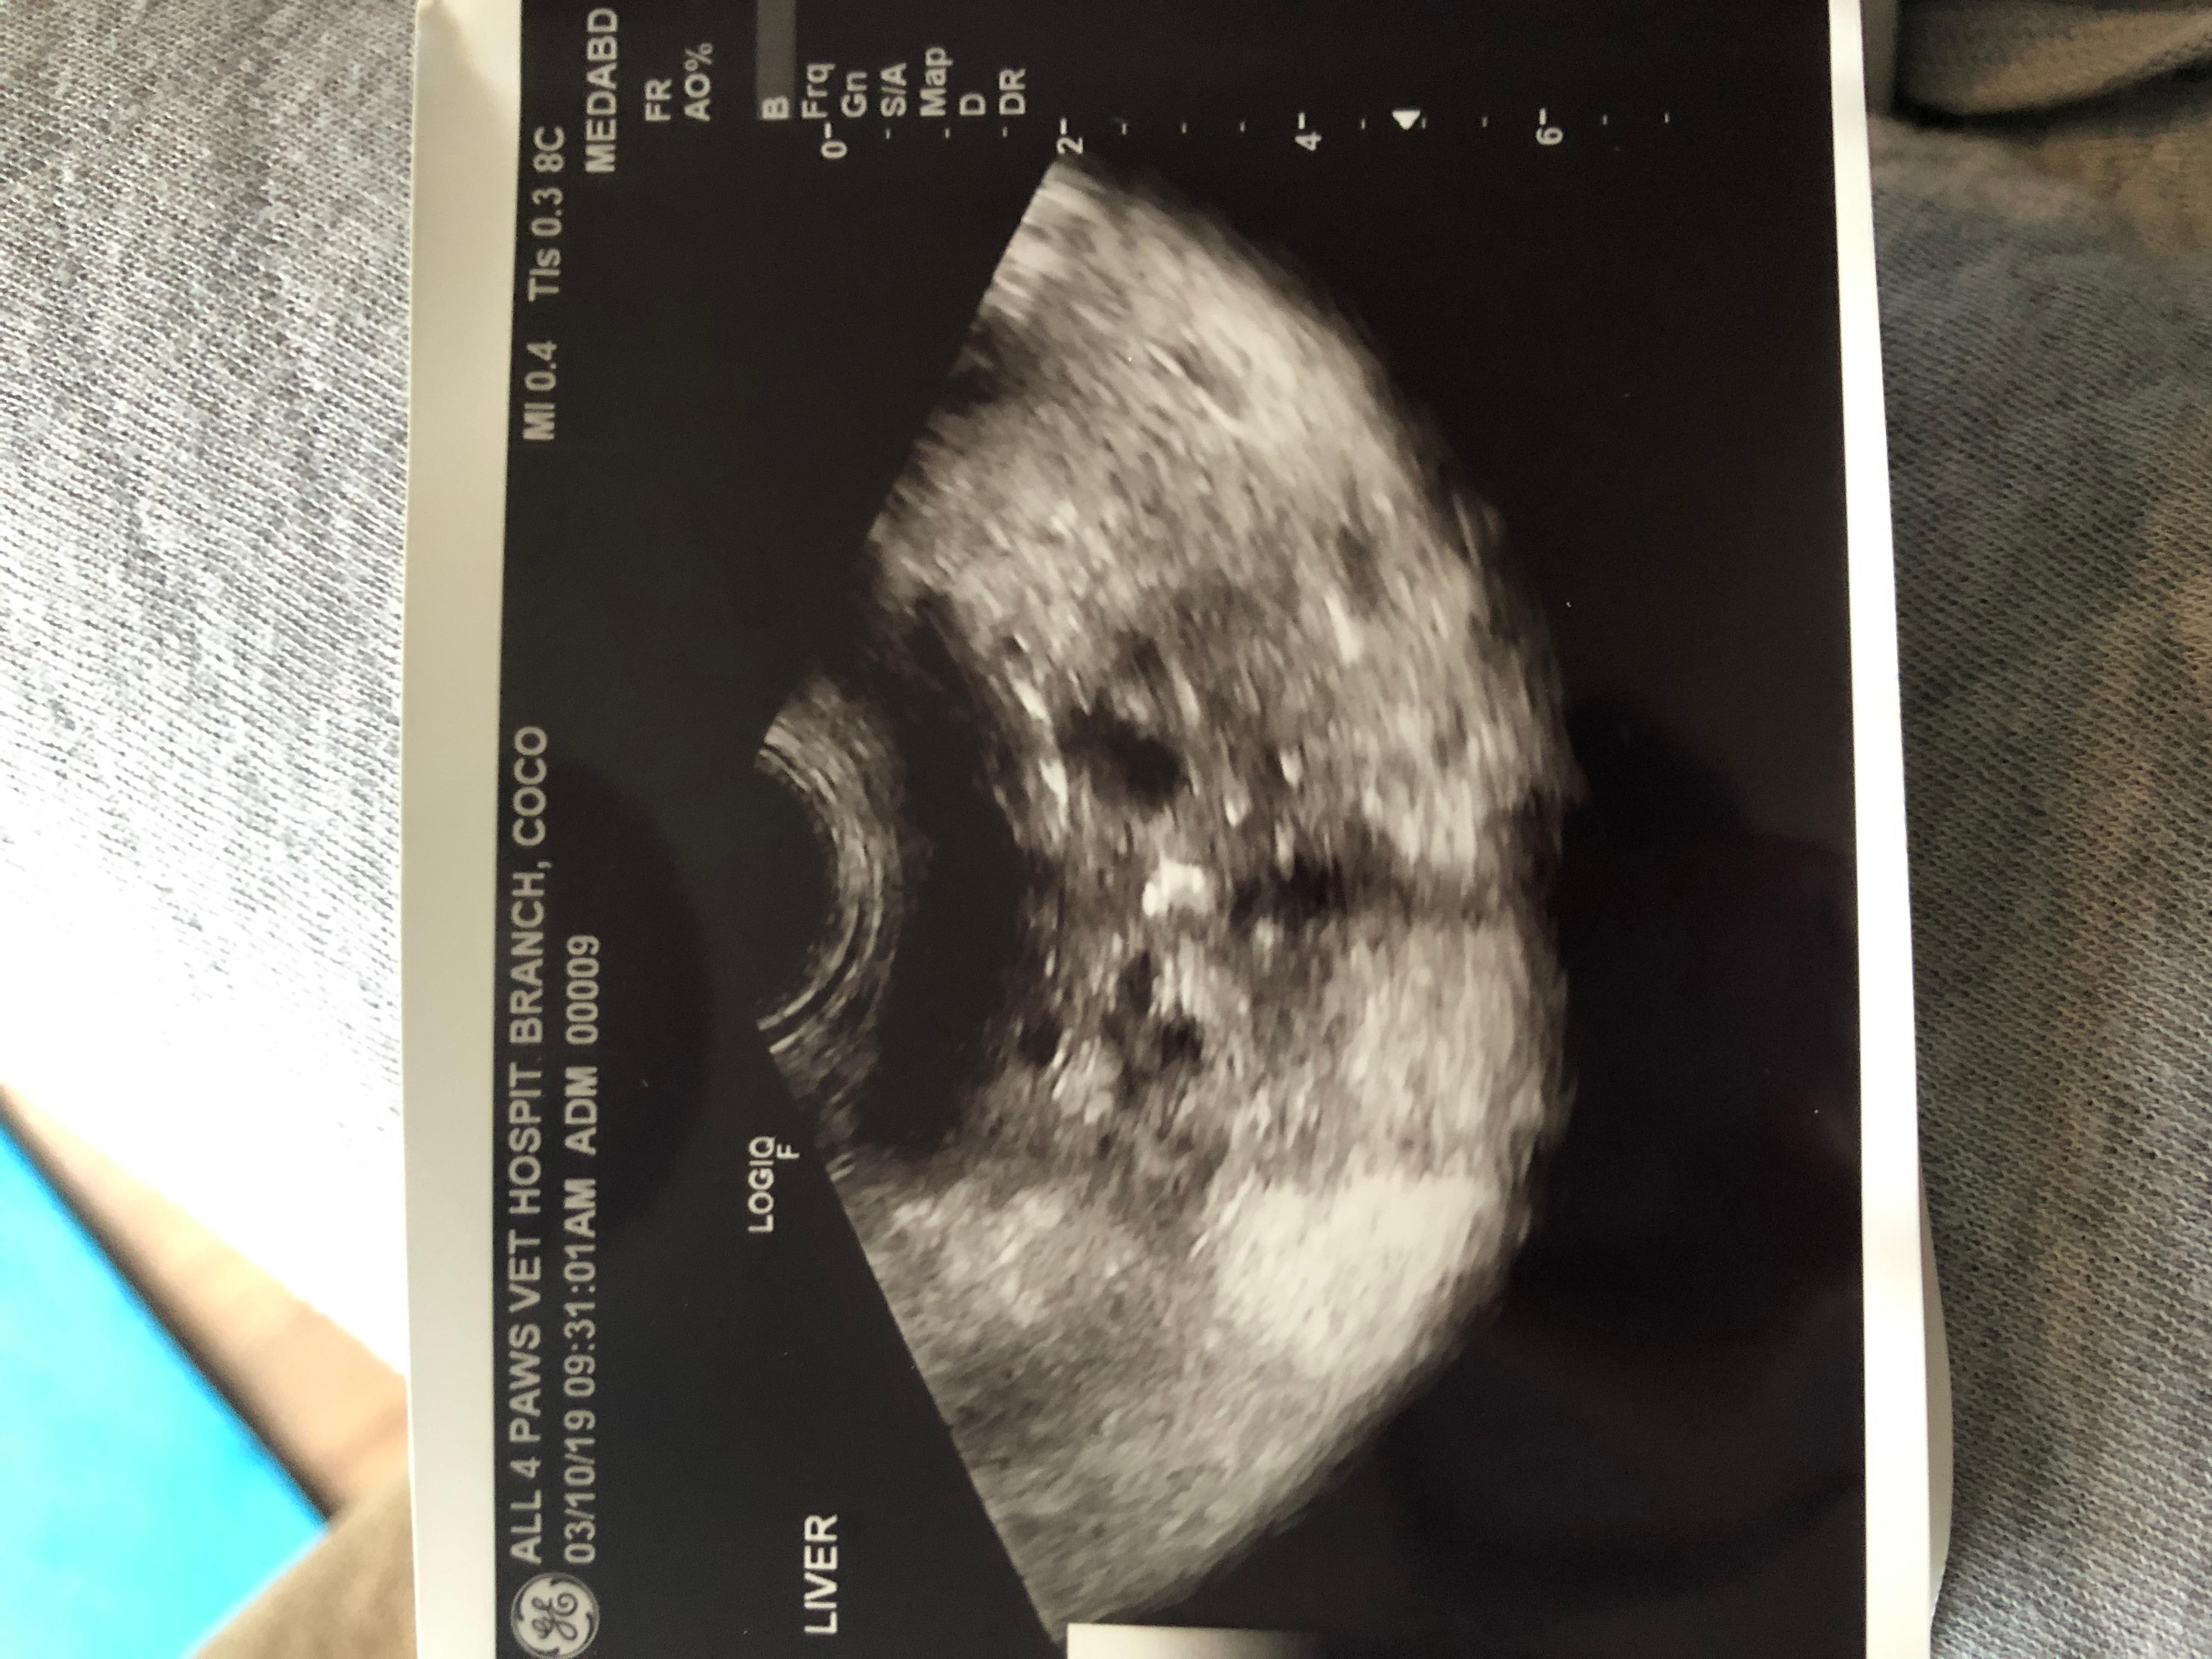

I took my dog to the vet again today and had x rays alongside an MRI done for her and they discovered that her liver (lobes?) looks abnormal. It appears to look like cheese and my doctor isn’t sure what it is exactly. I spent well over $2000 just to be shown this. Any guesses? Thanks

I see a still ultrasound picture in your photo, and while there are some hypoechoic areas that could make the liver look like Swiss cheese it is very difficult to interpret a single still ultrasound image. It’s possible that these are cysts, part of a tumor, blood vessels or enlarged bile ducts. Often a liver biopsy is necessary to determine what is ultimately causing liver abnormalities. I would recommend talking to your vet for clarification on what they think this could be and what the next steps might be.